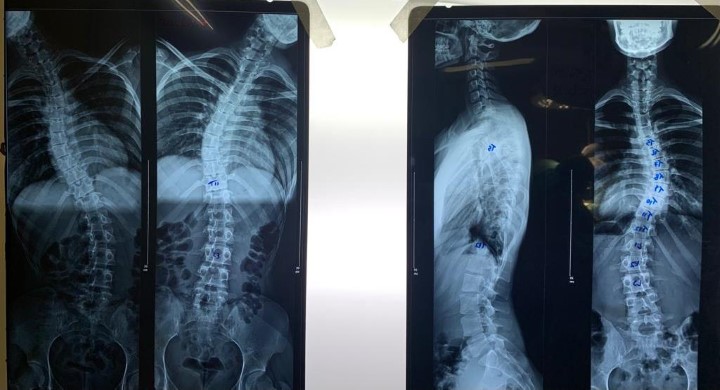

O Hospital Nossa Senhora das Dores (HNSD) realizou a primeira cirurgia para correção de escoliose idiopática com artrodese de Itabira. A paciente, uma mulher de 20 anos, passou por uma artrodese, que é uma fusão no local que apresentava as deformidades, onde foi colocado parafusos e hastes para manter a coluna o mais ereta possível. A cirurgia foi feita na última sexta-feira (7) e, segundo o médico responsável pelo procedimento, o ortopedista Glauber Henrique Costa Ferreira, “foi um grande sucesso”.

Ao todo, foram quatro horas de cirurgia, que contou com monitorização antes, durante e após o procedimento, com o objetivo de minimizar os riscos de lesão dos nervos e da medula. Ao final, devido ao protocolo para este tipo de cirurgia, considerada de grande porte, a paciente foi encaminhada para Unidade de Tratamento Intensivo (UTI), onde permaneceu por apenas um dia, sendo transferida na sequência para um apartamento. No último domingo (9), ela recebeu alta e conseguiu andar, o que atesta o sucesso de todo o tratamento.